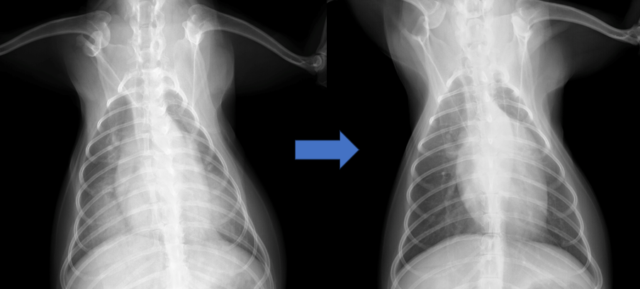

翌朝胸部レントゲン検査を行ったところ、肺野の改善が認められました。